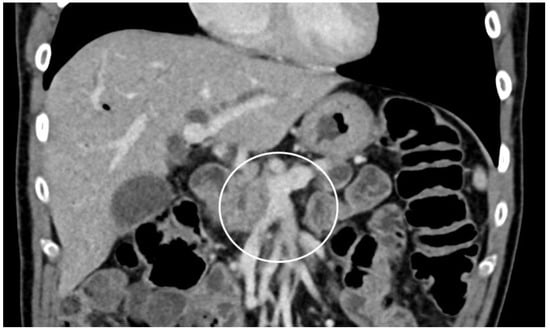

| Category | Anatomical Feature |

| Resectable: R | SMV/PV: no tumor contact or unilateral narrowing |

| SMA, CA, CHA: no tumor contact | |

| Borderline resectable: BR | Subclassified according to SMV/PV involvement alone or arterial invasion |

| BR-PV (SMV/PV involvement alone) | SMV/PV: tumor contact 180 or greater or bilateral narrowing/occlusion, not exceeding the inferior border of the duodenum. |

| SMA, CA, CHA: no tumor contact/invasion | |

| BR-A (arterial involvement) | SMA, CA: tumor contact of less than 180 without showing deformity/stenosis |

| CHA: tumor contact without showing tumor contact of the PHA and/or CA. | |

| Unresectable: UR | Subclassified according to the status of distant metastasis |

| Locally advanced: LA | SMV/PV: bilateral narrowing/occlusion, exceeding the inferior border of the duodenum |

| SMA, CA: tumor contact/invasion of 180 or more degree #. | |

| CHA: tumor contact/invasion showing tumor contact/invasion of the PHA and/or CA. | |

| AO: tumor contact or invasion. | |

| Metastatic: M | Distant metastasis $. |